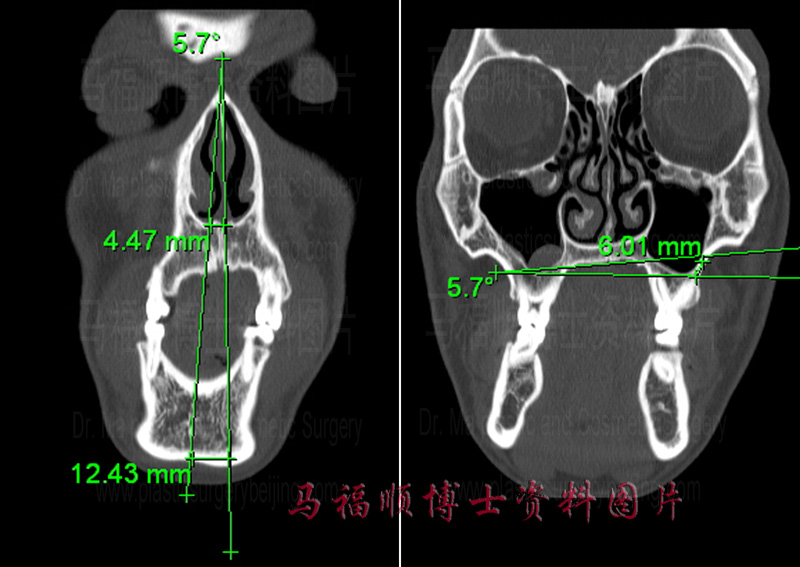

CT image of deviation facial deformity, the middle line of the chin goes away from the facial vertical line and the maxillary bone is not leveled.

The degree of facial bone deviation can be precisely measured in the CT image. The two vertical line in the left side photo are the facial middle line and the facial vertical line. The angle between these two lines is 5.7 degree. At the level of the chin tip the middle line swift to the right in about 12.5mm, at the level of the nasal base arouind 4.5mm. The two transverse lines in the right side photo depict the tilt degree of the maxillary bone. The height of the maxillary bone on the left side is 6mm higher than on the right side.